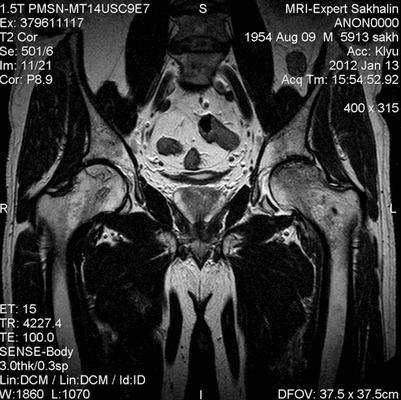

Рисунки 1,2. МР-картина артроза тазобедренных суставов с наличием отека костного мозга дистрофического характера в верхне-наружных отделах вертлужной впадины справа

Рисунок 3. МРТ тазобедренных суставов в косо-аксиальной плоскости.

Суставной хрящ головки бедренной кости и правой вертлужной впадины с обеих сторон однородной структуры, неравномерной толщины, целость его не нарушена. Головка бедренной кости сферичная, шейка не укорочена, не утолщена.